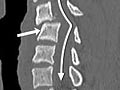

Computed Tomography (CT) Scan of the Spine

A CT scan uses X-rays to make detailed pictures of the spine and vertebrae.